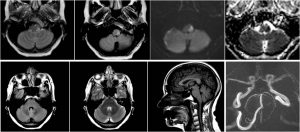

RM durante ingreso en NRL. Focalidad hiperintensa en T2 y FLAIR con restricción de la difusión en bulbo postero-lateral izquierdo. Ausencia de flujo en arteria vertebral izquierda intracraneal. Resto de exploración normal.

RM. Fila superior: Focalidad hiperintensa en T2 y FLAIR con restricción de la difusión (b1000 y ADC) en bulbo postero-lateral izquierdo: compatible con infarto agudo. Fila inferior: Secuencias axiales FLAIR y T2 a nivel del tronco y sagital T1 en linea media sin hallazgos patológicos valorables que sugieran rombencefalitis. AngioRM Phase-Contrast: ausencia de flujo en arteria vertebral izquierda intracraneal.